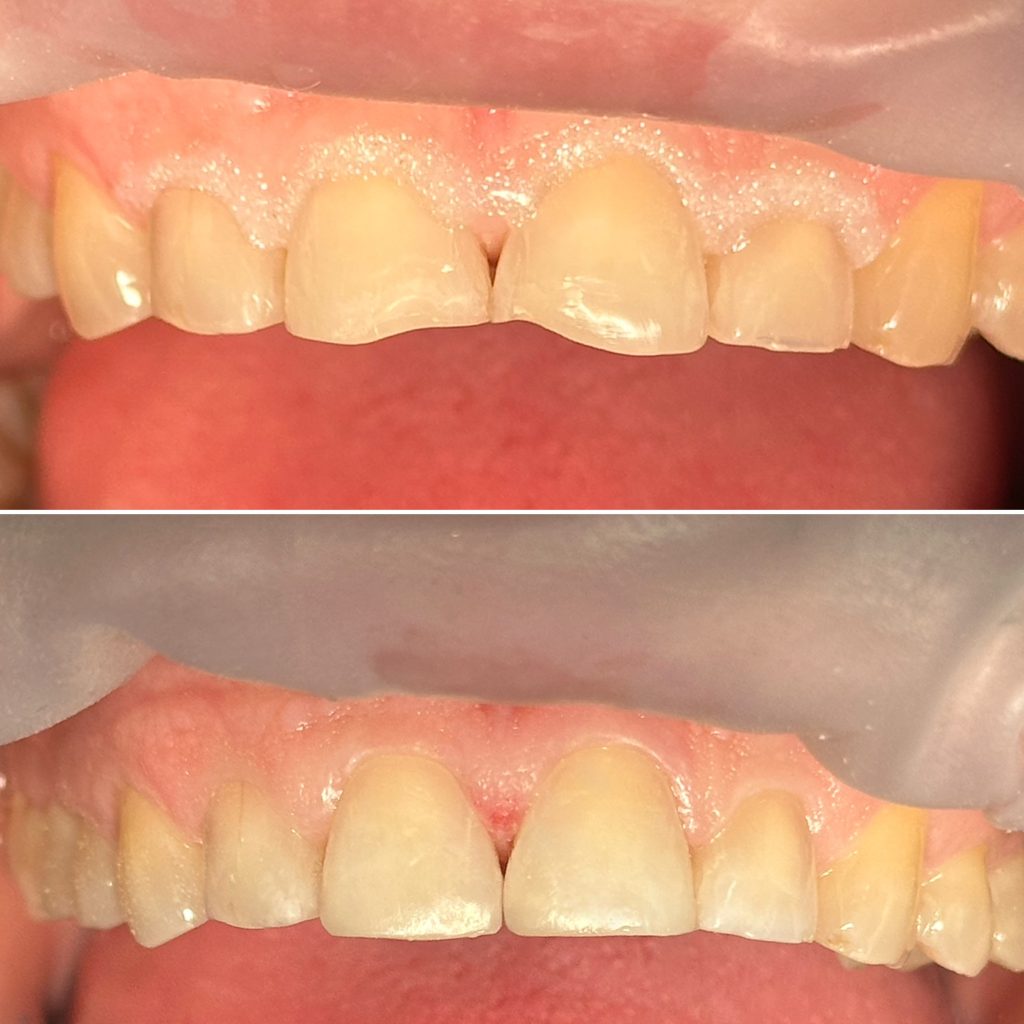

• Диагностика и лечение кариеса и его осложнений (пульпиты, периодонтиты)

• Художественная реставрация фронтального и бокового участка зубов